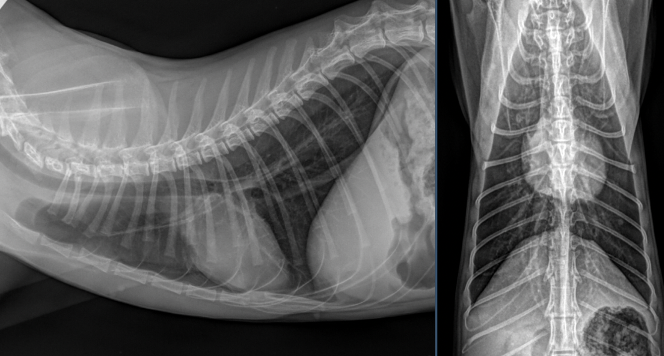

Besten Dank für die Übermittlung dieses spannenden Falles! Es liegen Röntgenbilder des Thorax und des Abdomens in 2 Ebenen vor (sinistro-dextraler Strahlengang, sowie ventro-dorsaler Strahlengang). Wesentliche Hauptbefunde sind im Bereich des muskuloskelettalen Systems, als auch im Abdomen zu vermerken.

Auffallend im Abdomenröntgen sind runde, homogene, weichteildichte Strukturen, die um die Harnblase lokalisiert sind und sich etwa auf Höhe von L5, sowie L6-7 (pinke Pfeile) befinden. Ihre Ausdehnung entspricht in etwa der Länge eines lumbalen Wirbelkörpers. Im kranialen Abdomen ist das seröse Detail zudem etwas reduziert. Im gesamten Verdauungstrakt findet sich weichteildichtes, teils auch mineraldichtes, granuliertes Material, begleitet von einer moderaten Menge an Luft (exemplarisch mit pinken Pfeilköpfen markiert). Freies abdominales Gas ist nicht nachweisbar und die Harnblase stellt sich intakt dar.

Trachea/Ösophagus, Mediastinum, Pulmonalgefäße, Aorta/V.cava, Pleuralraum, sowie alle abgebildeten ossären Strukturen stellen sich unauffällig dar. Die Herzsilhouhette misst im VHS 7,5 Wirbelkörper. Das Thoraxröntgen stellt sich somit unauffällig dar, ohne Hinweis auf Rippenfrakturen, Pneumothorax oder Lungenkontusionen.

Zusammenfassend ist hervorzuheben, dass es sich bei den weichteildichten Strukturen im kaudalen Abdomen sehr wahrscheinlich um multiple Fruchtblasen in beiden Uterushörnern handelt und somit der hochgradige Verdacht einer Trächtigkeit im Raum steht. Dies sollte unbedingt alsbald ultrasonographisch abgeklärt werden.